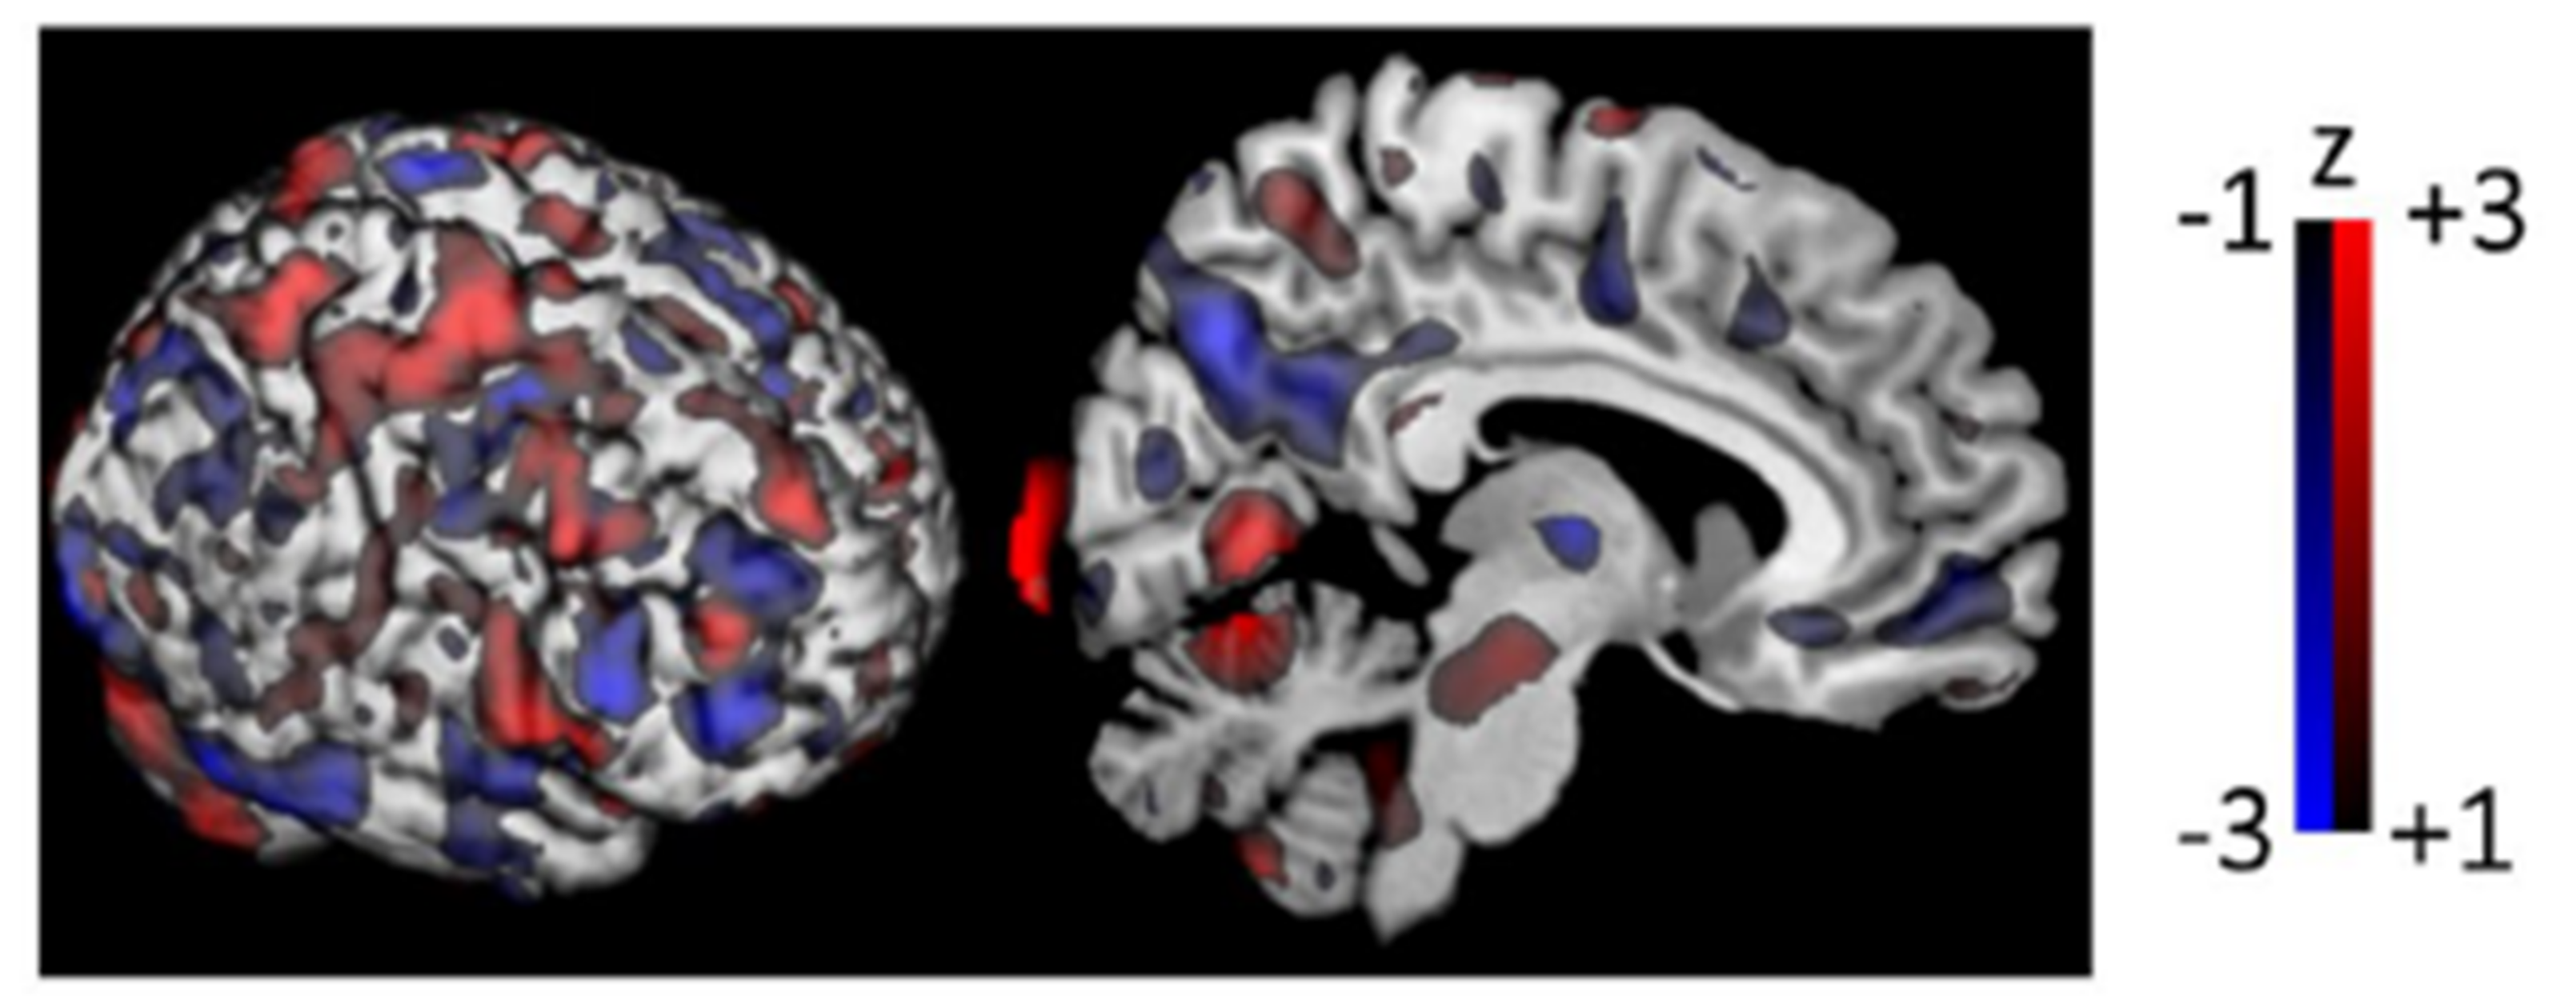

- Teune, K.L.; Strijkert, F.; Renken, J.R.; Izaks, J.G.; de Vries, J.J.; Segbers, M.; Roerdink, J.; Dierckx, R.; Leenders, L.K. The Alzheimer’s disease-related glucose metabolic brain pattern. Curr. Alzheimer Res. 2014, 11, 725–732. [Google Scholar] [CrossRef]

- Iizuka, T.; Kameyama, M. Spatial metabolic profiles to discriminate dementia with Lewy bodies from Alzheimer disease. J. Neurol. 2020, 267, 1960–1969. [Google Scholar] [CrossRef]

- Meles, S.K.; Pagani, M.; Arnaldi, D.; De Carli, F.; Dessi, B.; Morbelli, S.; Sambuceti, G.; Jonsson, C.; Leenders, K.L.; Nobili, F. Alzheimer’s disease metabolic brain pattern in mild cognitive impairment. J. Cereb. Blood Flow Metab. 2017, 37, 3643–3648. [Google Scholar] [CrossRef]

- Perovnik, M.; Tomše, P.; Jamšek, J.; Emeršič, A.; Tang, C.; Eidelberg, D.; Trošt, M. Identification and validation of Alzheimer’s disease-related metabolic brain pattern in biomarker confirmed Alzheimer’s dementia patients. Sci. Rep. 2022, 12, 11752. [Google Scholar] [CrossRef]

- Peretti, D.E.; García, D.V.; Renken, R.J.; Reesink, F.E.; Doorduin, J.; de Jong, B.M.; De Deyn, P.P.; Dierckx, R.A.J.O.; Boellaard, R. Alzheimer’s disease pattern derived from relative cerebral flow as an alternative for the metabolic pattern using SSM/PCA. EJNMMI Res. 2022, 12, 37. [Google Scholar] [CrossRef] [PubMed]